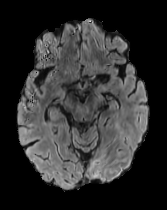

While ACAT revolves around generating counterfactuals, its primary strength lies in accurately identifying pathological regions, which are subsequently employed in a classification pipeline. On the other hand, it falls short in producing credible counterfactual examples, an issue we aim to address in this study. An illustration of this phenomenon is depicted in Figure 2, where we can observe how ACAT is able to generate a saliency map that approximately identifies the pathological region (e, bottom row). However, in the counterfactual example, the lesion remains visible (e, top row). In contrast, our approach not only refines the saliency map but also generates a counterfactual image where the pathology is completely eliminated (f).

In Figures 2 and 4 we display examples of healthy images and anomaly maps obtained with the different approaches. We can observe that f-Ano GAN is not able to generate credible counterfactuals and generally produces images of poor quality and unrealistic appearance. On the other hand, the approaches based on diffusion models are able to create more high-quality results. However, the ones obtained with CG and CFG seem to present some artifacts, which may not only impact the realism of the counterfactual examples but also the precision of the anomaly maps obtained from them. In order to better quantify the capability of these methods to accurately segment pathological areas, we compute the Dice scores of the anomaly maps they generate.